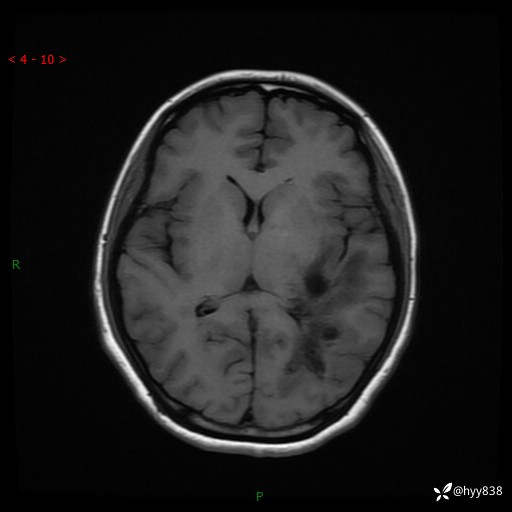

颅脑MRI平扫+增强